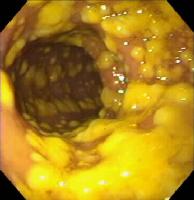

Pseudomembrane Colitis

Also referred to as Clostridium difficile-associated Disease (CDAD),

pseudomembrane colitis is an inflammation of the intestinal tract caused by the

toxins of Clostridium difficile. Toxin production damages the intestinal

lining, causing a pseudomembrane to form over top of the lining. Malabsorption

of nutrients and water result.